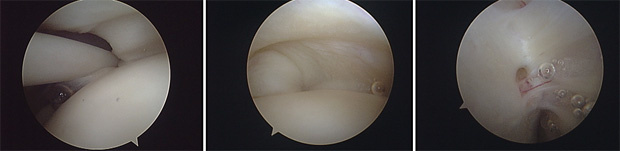

Após a avaliação do espaço articular, reposicionamos o artroscópio para avaliar o espaço subacromial. Nesse local, podemos identificar patologias da bursa subacromial, do manguito rotador, do acrômio, do ligamento coracoacromial e da articulação acrômioclavicular.

Apresentamos, a seguir, vídeos de procedimentos artroscópicos para bursectomia e acromioplastia, realizados em pacientes com Síndrome do Impacto Subacromial.